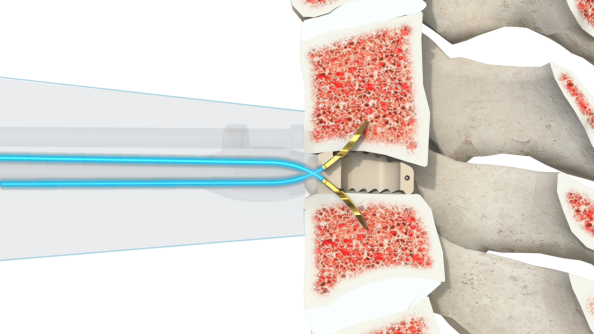

产品简介

Uni-C 插片式颈椎前路自稳定型融合器

• 国产首家取证插片式颈椎自稳定型融合器

• 垂直于骨面敲入固定夹,高低位颈椎不被骨结构遮挡操作

• 器械占位更小,配合脊柱内镜开展ACDF更加方便